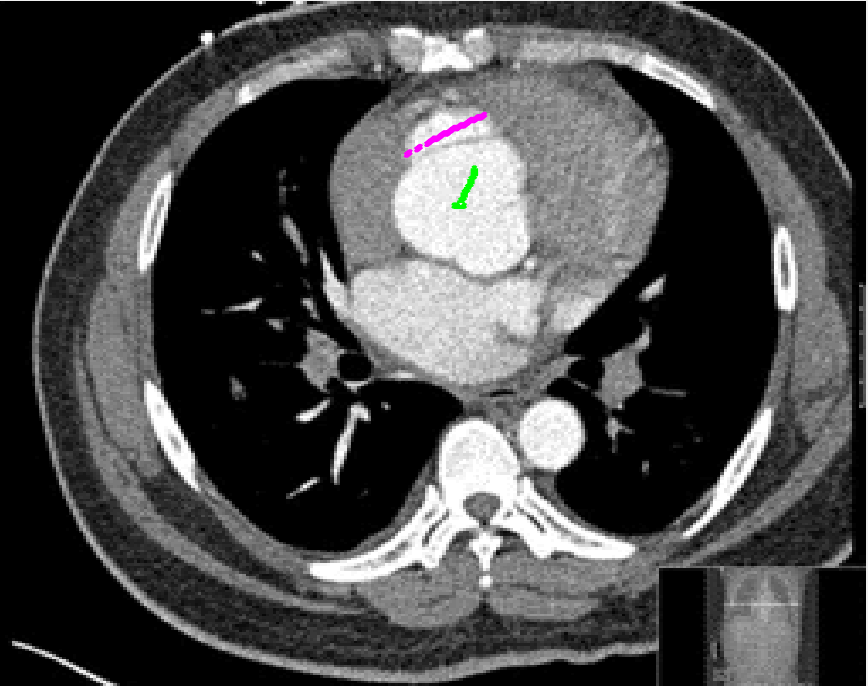

Four sets of test results are shown below. In Test 1 we compare models M1 – M6 to the proposed model M7 for two images which are hard to segment. The first is a CT scan from which we would like to segment the lower portion of the heart, the second is an MRI scan of a knee and we would like to segment the top of the Tibia. See Figure 9 for the test images and the marker sets used in the experiments. In Test 2 we will review the sensitivity of the proposed model to the main parameters. In Test 3 we will give several results achieved by the model using marker and anti-marker sets. In Test 4 we show the initialisation independence and marker independence of the Geodesic Model on real images.

In this test we give the segmentation results for models M1 – M7 for the two challenging test images shown in Figure 9. The marker and anti-marker sets used in the experiments are also shown in this figure. After extensive parameter tuning, the best final segmentation results for each of the models are shown in Figures 10 and 11. For M1 – M4 we obtain incorrect segmentations in both cases. In particular, the results of M2 and M4 are interesting as the former gives poor results for both images, and the latter gives a reasonable result for Test Image 1 and a poor result for Test Image 2. In the case of M2, the regularisation term includes the edge detector and the distance penalty term (see (4)). It is precisely this which permits the poor result in Figures 10(b) and 11(b) as the edge detector is zero along the contour and the fitting terms are satisfied there (both intensity and area constraints) – the distance term is not large enough to counteract the effect of these. In the case of M4, the distance term and edge detector are separated from the regulariser and are used to weight the Chan-Vese fitting terms (see (9)). The poor segmentation in Figure 11(b) is due to the Chan-Vese terms encouraging segmentation of bright objects (in this case), weighting enforces these terms at all edges in the image and near . In experiments, we find that M4 performs well when the object to segment is of approximately the highest or lowest intensity in the image, however when this is not the case, results tend to be poor. We see that, in both cases, models M5 and M6 give much improved results to M2 and M4 (obtained by incorporating the geodesic distance penalty into each). The proposed Geodesic Model M7 gives an accurate segmentation in both cases. It remains to compare M5, M6 and M7. We see that M5 is a non-convex model (and cannot be made convex [39]), therefore results are initialisation dependent. It also requires one more parameter than M6 and M7, and an accurate set to give a reasonable area constraint in (4). These limitations lead us to conclude M6 and M7 are better choices than M5. In the case of M6, it has the same number of parameters as M7 and gives good results. M6 can be viewed as the model M7 with weighted intensity fitting terms (compare (18) and (30)). Experimentally, we find that the same quality of segmentation result can be achieved with both models generally, however M6 is more parameter sensitive than M7. This can be seen in the parameter map in Figure 12 with M7 giving an accurate result for a wider range of parameters than M6. To show the improvement of M7 over previous models, we also give an image in Figure 13 which can be accurately segmented with M7 but the correct result is never achieved with M6 (or M3). Therefore we find that M7 outperforms all other models tested M1 – M6.

Test 3 – Further Results from the Geodesic Model M7. In this test we give some medical segmentation results obtained using the Geodesic Model M7. The results are shown in Figure 14. In the final two columns we use anti-markers to demonstrate how to overcome blurred edges and low contrast edges in an image. These are challenging and it is pleasing to see the correctly segmented results.

(i) (ii) (iii) (iv) (v)